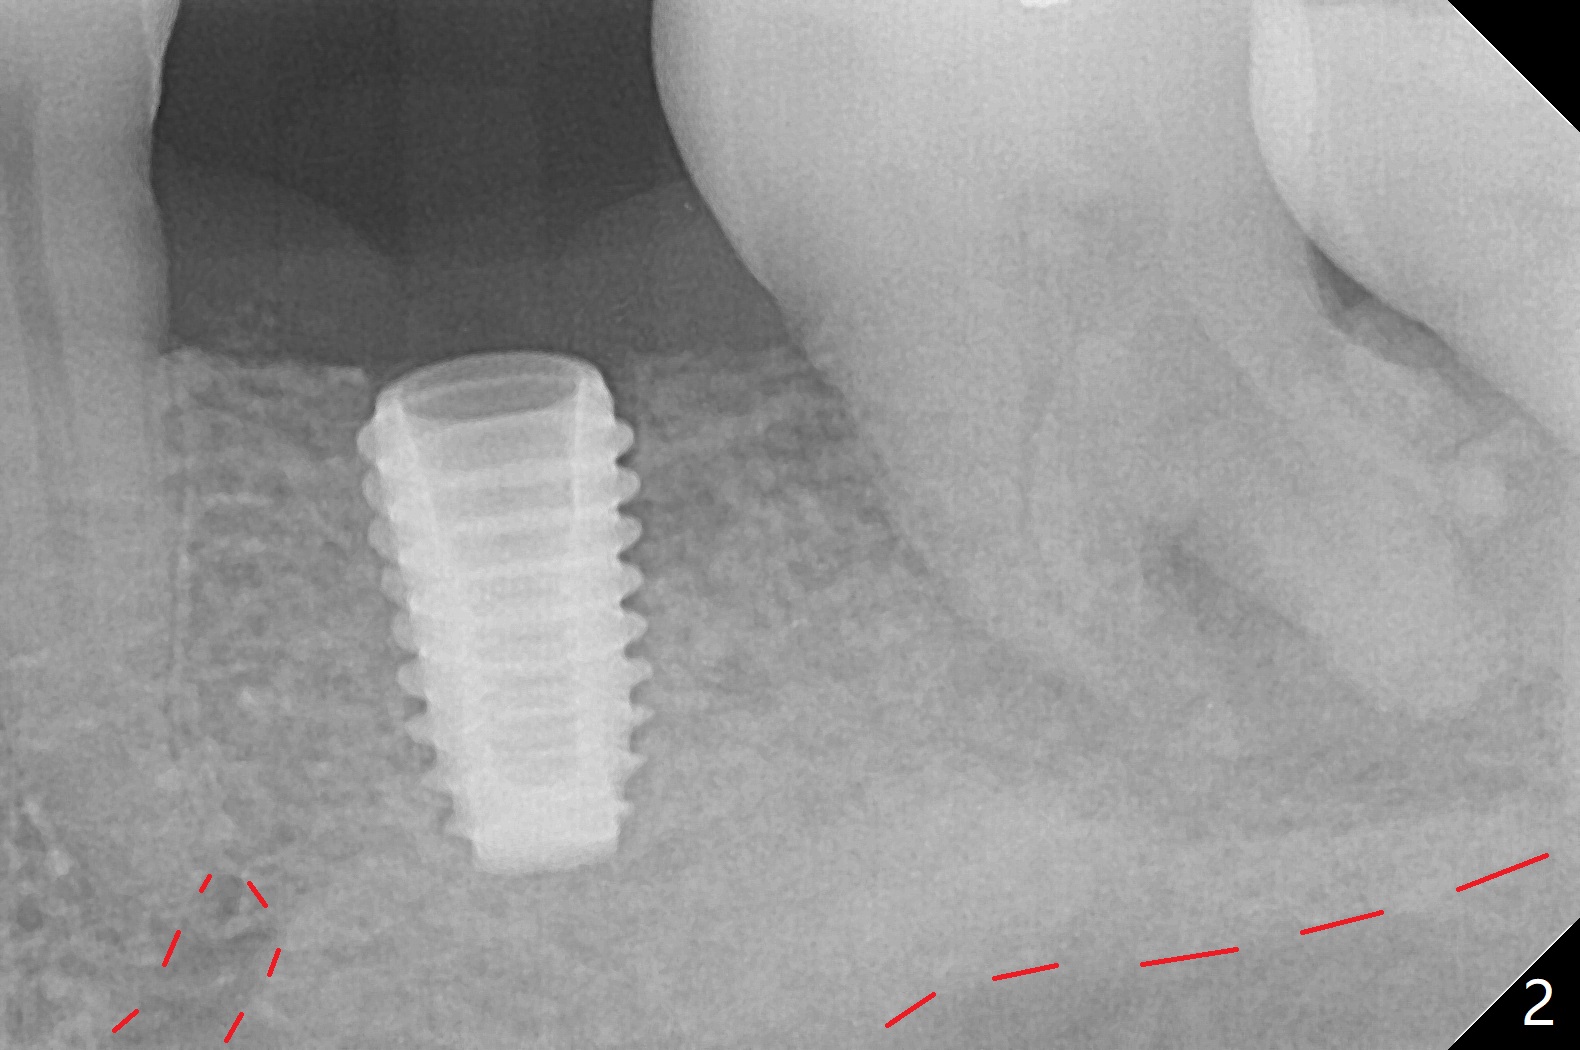

After use of 4.5x8.5 mm guide drill at #19, a 5x8.5 mm implant is placed with guide in place. When the latter is removed, the implant is found to be placed shallow. Following use of 4.5x10 mm drill for ~.75 mm deeper, the implant returns with deeper placement (Fig.1,2), confirmed after guide removal. The implant is further torqued 3 more times with visual confirmation of implant deeper placement. After seating a 5.5x5(3) mm healing abutment, autogenous bone graft is placed between the gingiva and the abutment to reduce chance of periimplantitis. The patient reports more severe pain (bone burn?) than free-hand placement at #30. In fact there is no bone loss around the implant 10.5 months postop (Fig.3).